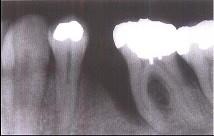

问题 牙槽骨垂直型吸收的特点,除外 ( )

选项 A.牙槽骨不发生水平方向的吸收 B.牙槽骨发生垂直或斜型方向的吸收 C.与牙根面形成角型的骨缺损 D.牙槽嵴高度降低不多,而牙根周围的骨吸收较多 E.垂直吸收多形成骨下袋

答案 A